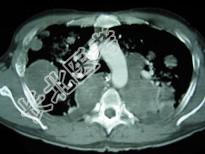

- 单项选择题33岁,男, 咳嗽1周,有骨肉瘤病史, 请结合胸片和CT图,选出最可能的诊断 ( )

C、骨肉瘤转移